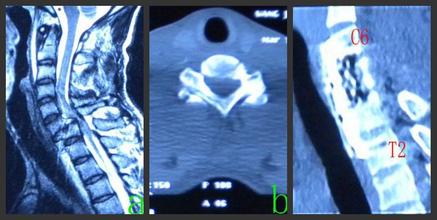

2.CT檢查

對(duì)于骨折不明確但又不能排除者、脊柱骨折有可能壓迫脊髓神經(jīng)根者及復(fù)雜骨折者均可行CT檢查。三維CT重建可以更直觀便捷地進(jìn)行骨折分型,對(duì)治療方案選擇幫助很大,目前臨床上常用。

3.MRI檢查

雖然顯示骨折線不如CT檢查,但對(duì)于脊髓神經(jīng)根及軟組織損傷的顯示有獨(dú)特優(yōu)點(diǎn),目前已廣泛用于脊柱骨折的檢查。